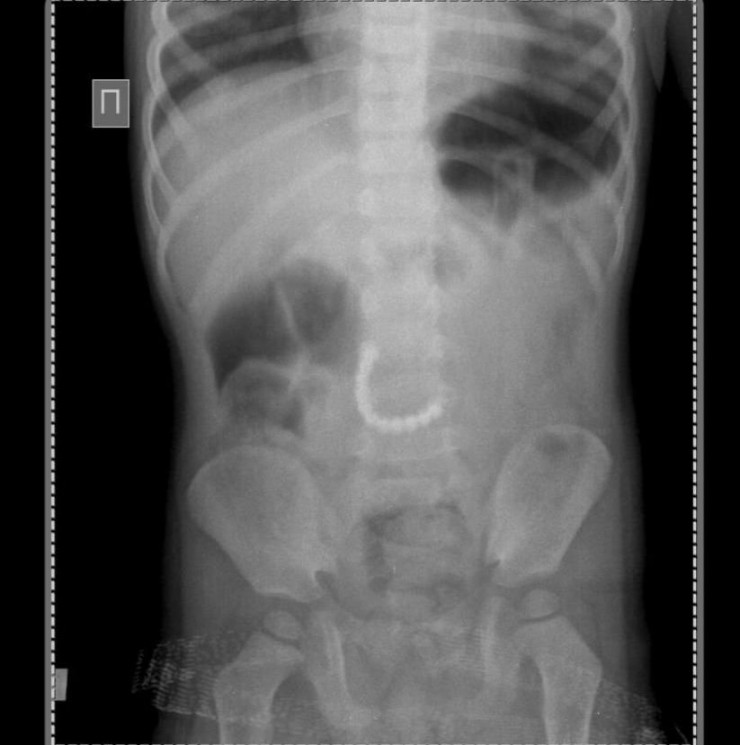

Карагандинские врачи извлекли из брюшной полости двухлетнего малыша 11 магнитов. Ребенок поступил в областную детскую больницу в экстренном порядке 4 февраля. У него были сильные боли в животе, его неоднократно рвало. Рентгенография органов брюшной полости показала наличие в ней инородных тел.

"В экстренном порядке проведена сложная операция, в ходе которой обнаружено повреждение (перфорация- прим.) тощей кишки. Из желудочно-кишечного тракта малыша удалось извлечь магнитные детали от детских игрушек в количестве 11 штук. Именно они и повредили кишку и склеились между собой", - рассказал заместитель директора по хирургической службе областной детской клинической больницы Жанат Елубаев.